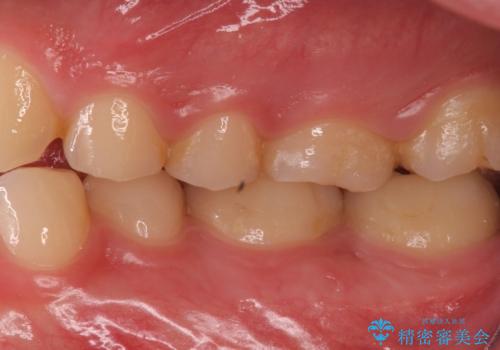

奥歯がしみる 神経を温存する治療

- 奥歯がしみるとのことで来院されました。

検査の結果、古い詰め物の裏側に虫歯ができていること(二次う蝕)が確認されたため、治療していくこととなりました。

虫歯が大きくても、今回のように神経を温存することができる場合があります。